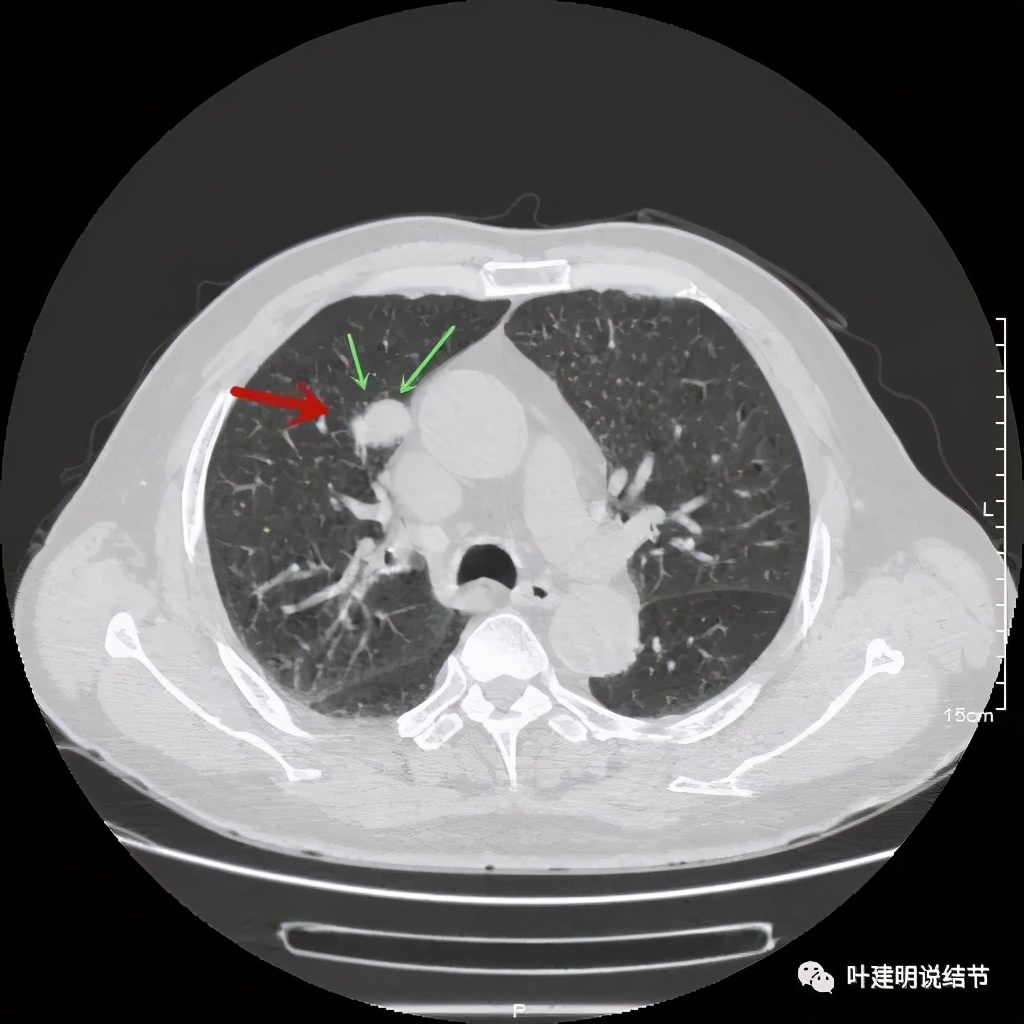

上图示病灶边缘过于光滑(绿色);局部有点状钙化(蓝色)

上图示病灶边缘过于光滑(绿色);血管贴边(桔色);

上图示病灶边缘过于光滑(绿色);血管贴边走行(桔色)

以上几图也示病灶边缘过光(绿色);血管贴边,感觉没受侵犯(桔色)

事前来看,达2.4厘米的不均质实性肿块,增强有轻度不均匀强化,血管贴边走行,支气管疑有截断,恶性不能除外,而且可能性较大。但现在经过手术已已经证实是错构瘤的情况下,我们回头来看,其实有许多不符合恶性的地方:

1、病灶的每个层面,边缘都过于光滑了。肺癌一般到这个大小总要有棘突、分叶、毛刺、牵拉周围胸膜等边缘异常的征象;

2、肿瘤大于2厘米以上,又紧贴血管,多有血管走行异常、受侵或血管进入等征象;

其实我们发现,包括今天这例,只要是错构瘤,“边缘非常光滑”是每一像都具备的!虽然有的似有支气管截断、有的似有血管征、有的似有分叶,但总的只要是边缘非常光滑的实性占位,就要想到错构瘤的可能,若有点状钙化密度,更是强烈要考虑。错构瘤如何靠近胸膜,其实可以切开一点肺实质,挤一下,肿瘤就会滚出来。